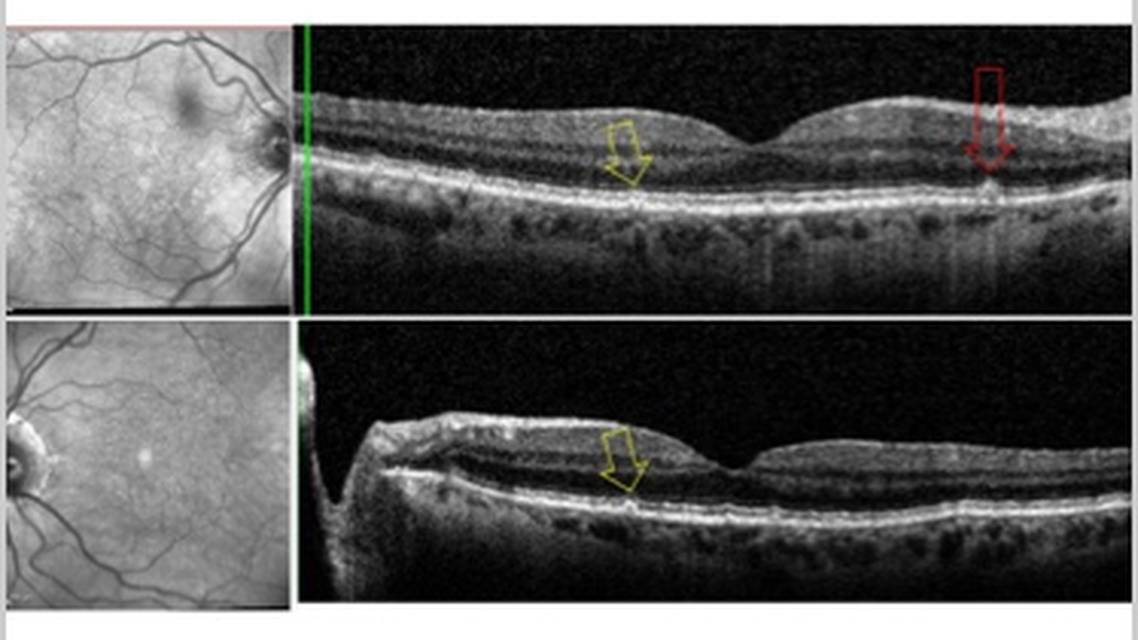

The patient's entering BCVA was 20/30 OD and 20/40 OS, improving to 20/25 OU with refraction. Anterior segment examination revealed early cataracts OU and mild signs of dry eyes. Fundus examination showed signs of hypertensive retinopathy and early age-related macular degeneration (AMD) with the presence of small drusen and mild retinal pigment epithelium (RPE) changes in both eyes. Baseline imaging with optical coherence tomography (OCT) confirmed these findings (Figure 1).

Fundus examination and OCT revealed progression to advanced AMD in both eyes. In the right eye, there were small-to-large sized drusen with pigment changes and subretinal pigment clumping with overlying scant subretinal fluid, indicative of macular neovascularization (MNV). In the left eye, small-to-large sized drusen with pigment changes were observed, along with multiple areas of geographic atrophy (GA) lesions (Figure 2).

At her 3-month follow-up visit, the right eye, treated for wet AMD with ongoing intravitreal anti-VEGF injections, showed improvement with VA reaching 20/50. OCT imaging confirmed stabilization of subretinal fluid and reduction in a pigment epithelial detachment (Figure 3). The left eye with GA was being monitored for progression and had a VA of 20/40. Fundus examination revealed well-demarcated areas of RPE and outer retinal atrophy. OCT imaging of the left eye demonstrated expanded areas of choroidal hypertransmission, indicating progression of RPE loss, along with thinning of the outer nuclear layer and disruption of the ellipsoid zone in areas of GA (Figure 3).

Unfortunately, the patient missed her scheduled 3-month follow-up in February 2024. It was later discovered that she had been referred for and underwent cataract surgery in her left eye. The patient was most recently seen in June 2024, with visual acuity improved to 20/25 in both eyes. However, despite the improved acuity in the left eye after cataract surgery, the patient reported persistent blurry vision in her left eye. Updated OCT imaging revealed further expansion of GA lesions in the left eye, while the wet AMD in the right eye had resolved (Figure 3). This visit underscored the disconnect between visual acuity measurements and functional vision in GA, as well as the potential risks of interrupting consistent follow-up and deferring treatment.